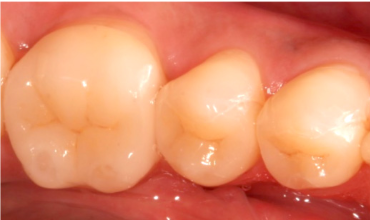

レジン充填法(保険・自費)

• 治療前

• 治療後

一般的に虫歯治療の際に利用する「詰め物」は銀歯をイメージされるかと思いますが、当院では白い素材(レジン)を利用します。次のような特徴があります。

✅「ゲル状」なので削る量を最小限に抑えられる

✅「1回の来院」で治療が終了

保険適用の素材と、レジンにセラミックの材質を入れ込んだ、より審美性が高い素材を利用した自費治療(16,500円~/税込)の2つから選択できます。